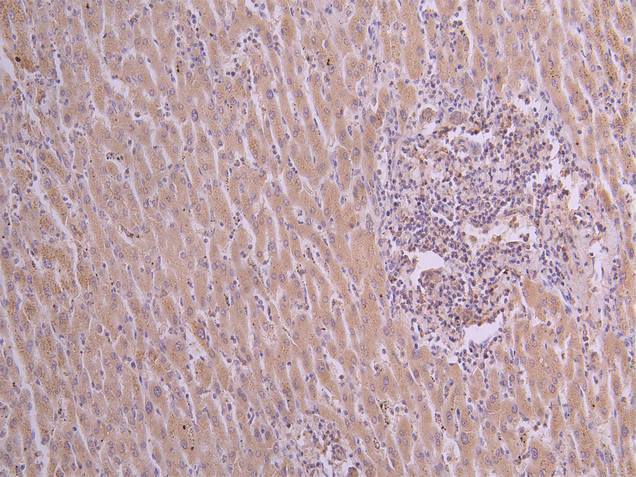

IHC image of CSB-RA025833MA1HU diluted at 1:50 and staining in paraffin-embedded human liver cancer performed on a Leica BondTM system. After dewaxing and hydration, antigen retrieval was mediated by high pressure in a citrate buffer (pH 6.0). Section was blocked with 10% normal goat serum 30min at RT. Then primary antibody (1% BSA) was incubated at 4°C overnight. The primary is detected by a Goat anti-human polymer IgG labeled by HRP and visualized using 0.05% DAB.